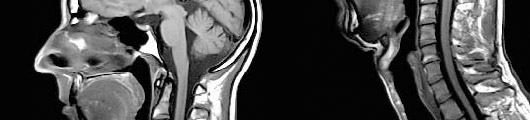

High quality RF coils and an optimized RF chain allow image acquisition with up to 8 channels and up to 16 CP coil elements. All array coils are iPAT compatible, for faster, higher differentiated and more clinically relevant images.

Integrated Panoramic Array (lPA) allows flexible combinations of up to 16 CP coil elements from up to 4 different coils. Patients and technologists will enjoy the easy handling and set-up time: the lower port of the CP Head Array Coil and the entire CP Spine Array Coil stay on the table for many exams.

• MRI produces the clearest and most detailed images possible of soft-tissue structures of the body (e.g., the heart, lungs and liver). The high level of detail makes MRI an invaluable tool in early diagnosis and evaluation of tumors. It also reveals abnormalities that can be obscured by bone with other imaging methods.

• MRI can help physicians evaluate the function as well as the structure of many organs.

• MRI offers a fast, noninvasive alternative to x-ray angiography for diagnosing problems ofthe heart and cardiovascular system.

• MR angiography (MRA) offers fast three-dimensional (3D) single breath-hold sequences for contrast enhanced MRA. As there is no radiation exposure, minimal invasivity and short examination time with high accuracy, MRA represents an alternative to digital arteriography.